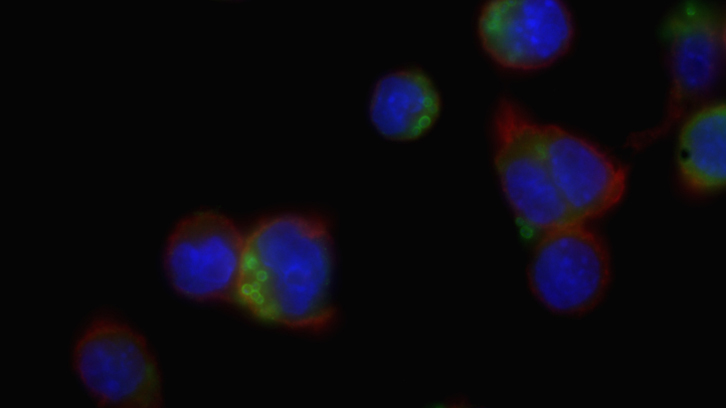

Des de fa un cert temps, s’ha replantejat l’ús de bacteriòfags, els quals són virus que infecten exclusivament als bacteris, com alternativa als antibiòtics o com a mesura complementària....